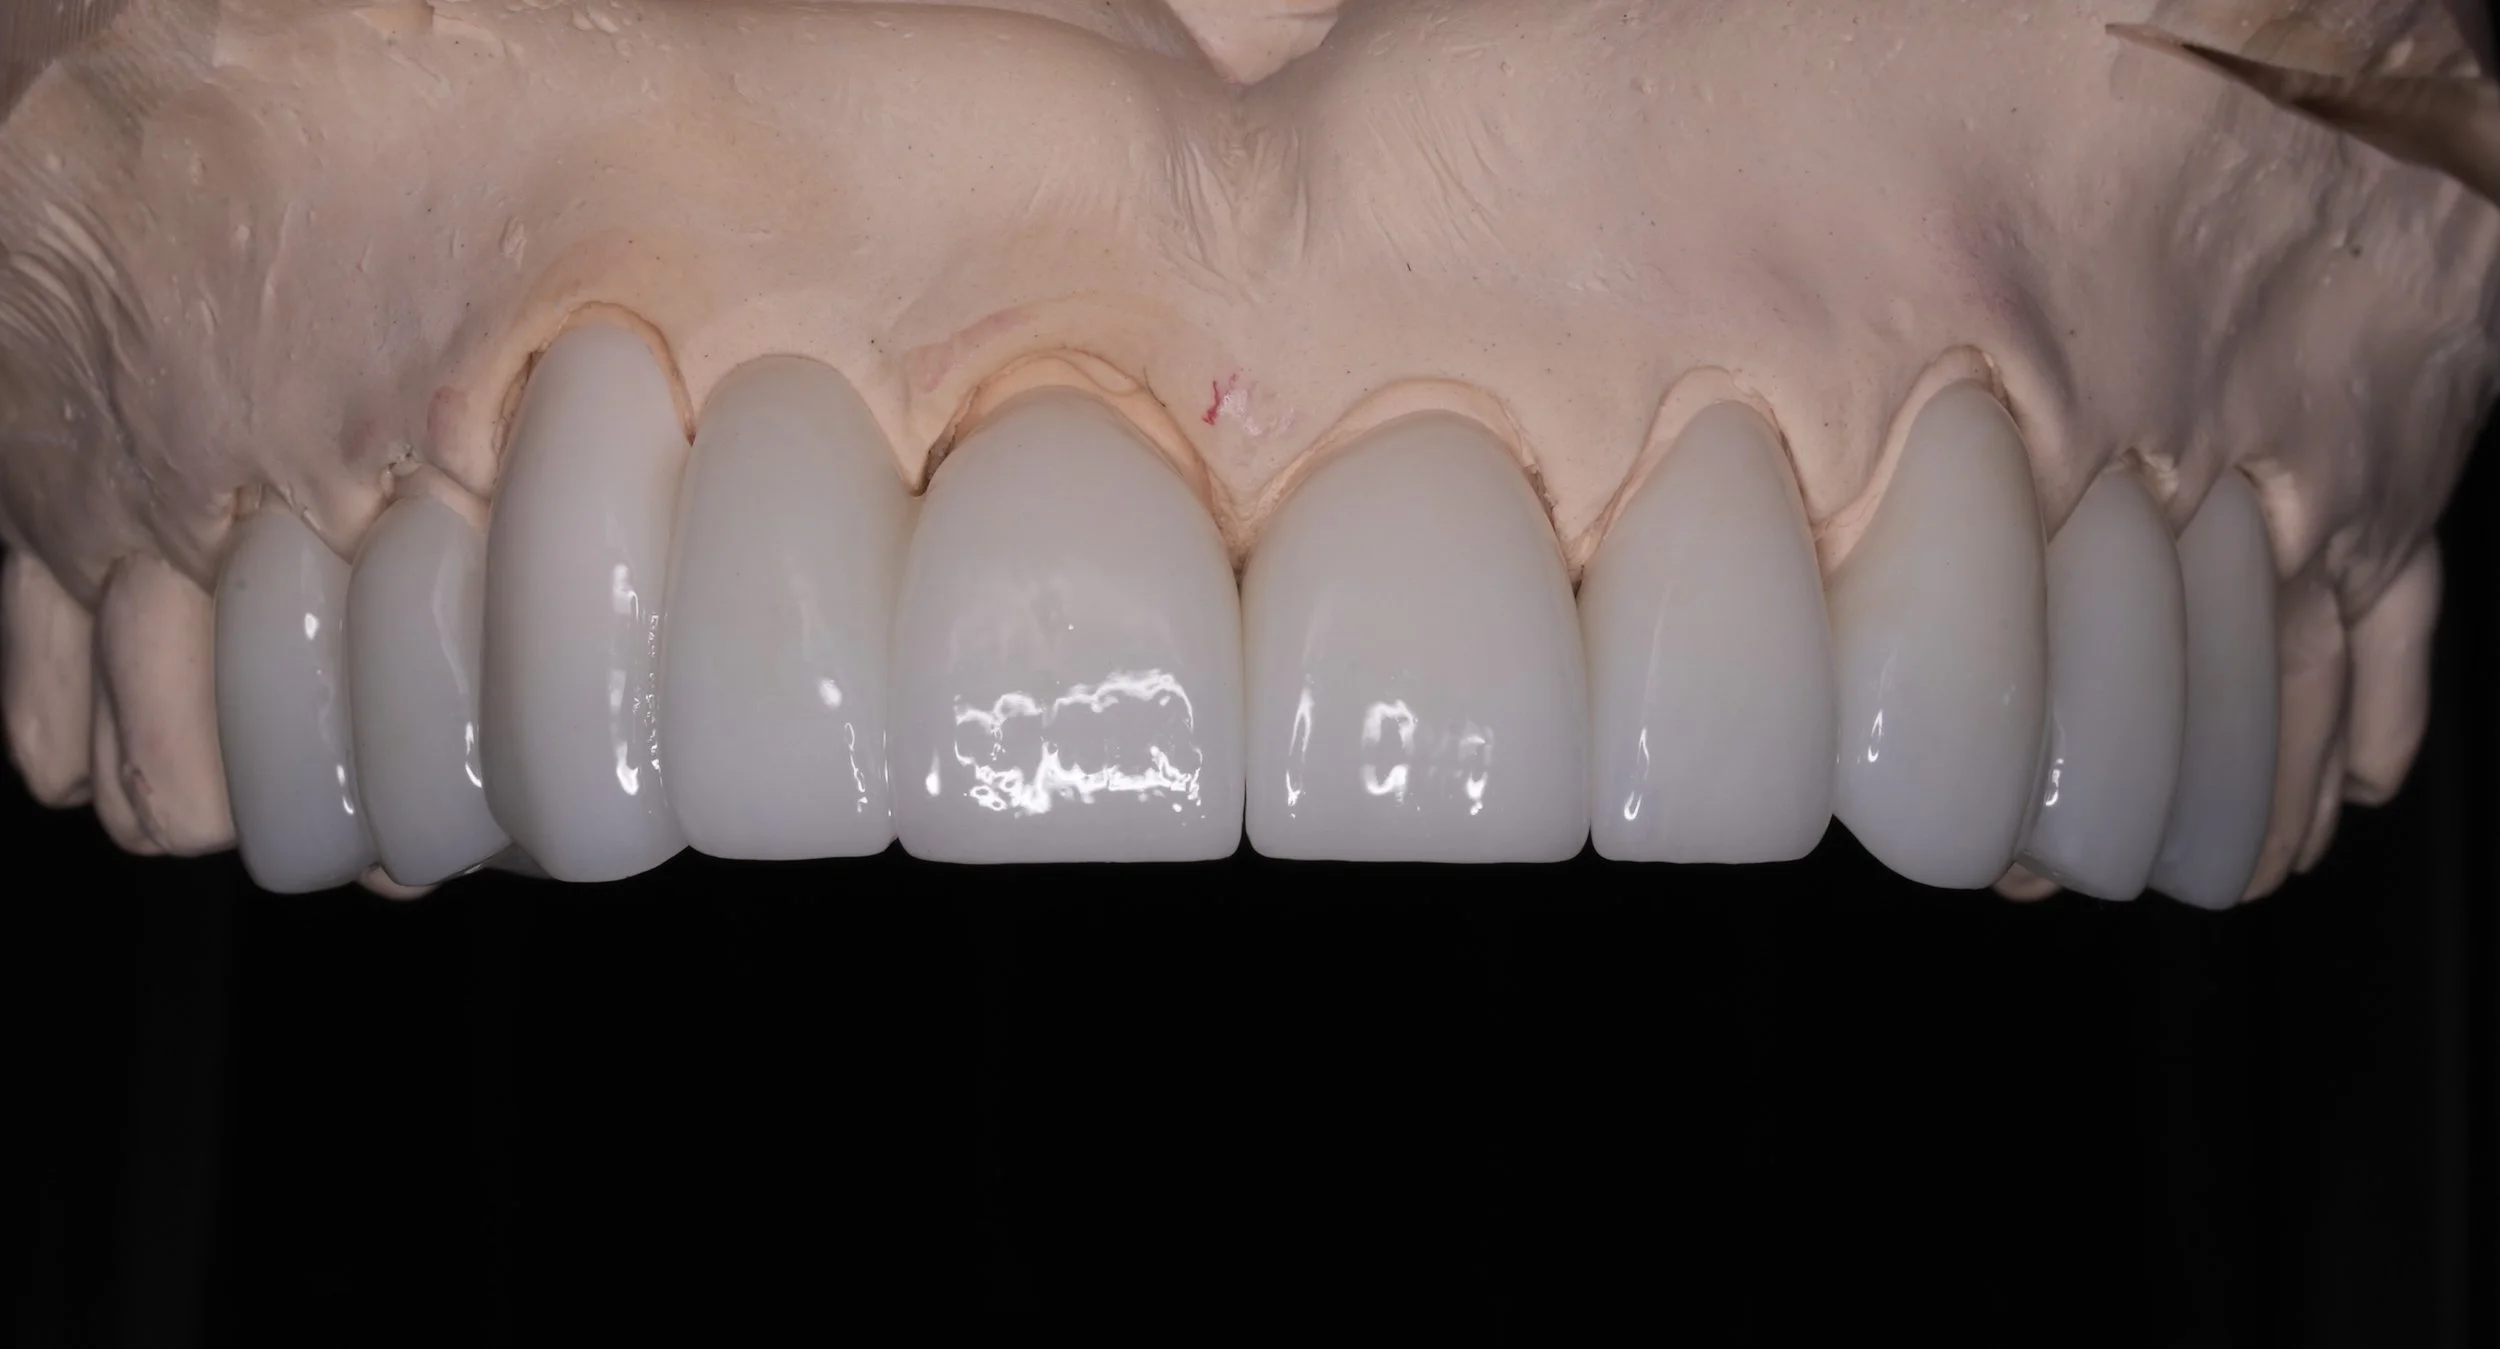

Fixed pros